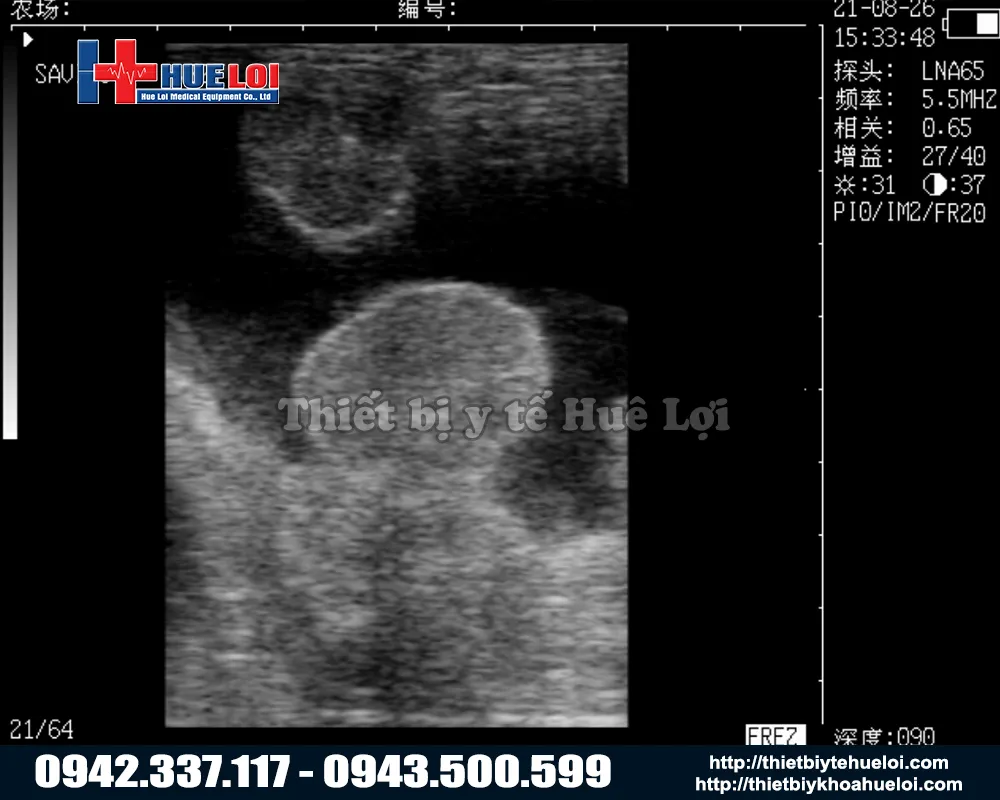

Máy siêu âm xách tay WELL.D M3V là giải pháp chẩn đoán thai và đo độ dày mỡ lưng di động hàng đầu, được thiết kế chuyên biệt cho ngành chăn nuôi lợn hiện đại. Máy sử dụng công nghệ sóng âm tần số cao, thiết bị cho phép tầm soát thai sản và kiểm tra nội tạng một cách an toàn, chính xác và hoàn toàn không xâm lấn. Với kết cấu bền bỉ, nhỏ gọn cùng pin sạc tiện dụng, M3V đóng vai trò như một 'phòng khám di động', hỗ trợ bác sĩ thú y đưa ra kết quả tức thì ngay tại chuồng trại mà không cần di chuyển vật nuôi.

2. Công Nghệ Hình Ảnh "Mimage" Vượt Trội

Dù là máy cầm tay nhỏ gọn, M3V được trang bị nền tảng siêu âm y tế với công nghệ hình ảnh "Mimage", mang lại chất lượng hình ảnh chẩn đoán sắc nét và rõ ràng đáng kinh ngạc. Với màn hình LCD 7 inch lớn so với các dòng cầm tay (thường chỉ 5-5.5 inch). Tỷ lệ 16:9 giúp việc quan sát các chi tiết nhỏ trở nên dễ dàng hơn bao giờ hết.